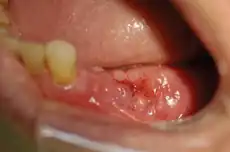

MRONJ Staging Criteria* (>8 weeks) Treatment Strategies** Picture

Stage 1 Exposed and necrotic bone, or fistulae that probes to bone, in patients who are asymptomatic and have no evidence of infection Antibacterial mouth rinse, Clinical follow-up on a quarterly basis, Patient education and review of indications for continued bisphosphonate therapy